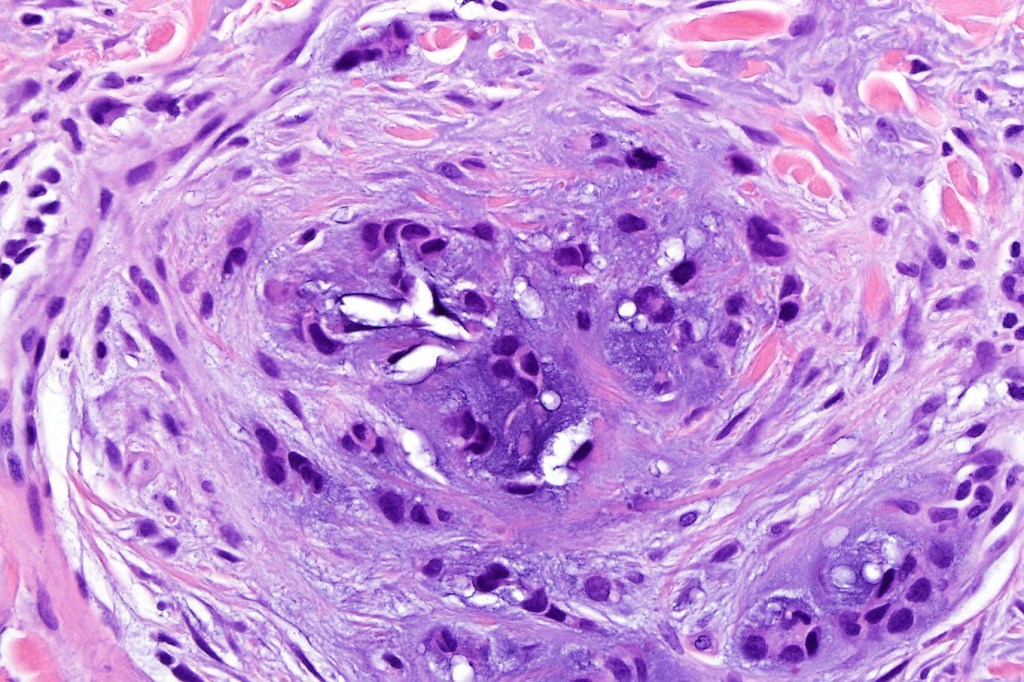

•Well circumscribed unencapsulated, nodular/multinodular silhouette composed of an admixture of epithelial & mesenchymal elements

•Often intensely basophilic due to mucinous deposits

•Mixed epithelial component including nests & cords of epithelium with abundant, eosinophilic cytoplasm & small vesicular nuclei

•Glandular differentiation sometimes showing apocrine differentiation

•Myoepithelial layer in glandular foci

•Ductal differentiation

•Stromal sclerosis & hyalinization

•Myxoid change

•Chondroid foci

•Calcification & osteoid